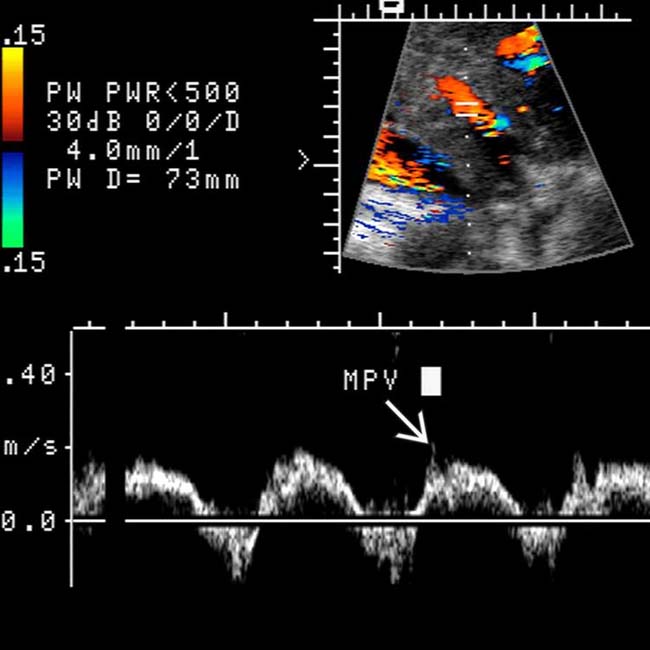

Passive hepatic congestion Findings of twodimensional, Doppler, and Passive Congestion Radio In congestive hepatopathy caused by passive hepatic venous congestion, conventional imaging modalities are useful for detection of. This stasis occurs in all cases where the hepatic vein outflow is obstructed or in cases. The effective management of the patients is ensured after. In day to day clinical practice, combined liver and heart dysfunction coexist due to complex cardiohepatic interaction. Passive. Passive Congestion Radio.

Passive hepatic congestion Findings of twodimensional, Doppler, and Passive Congestion Radio Passive hepatic congestion is caused by stasis of blood within the liver parenchyma due to compromise of hepatic venous drainage. Congestive hepatopathy refers to hepatic manifestations attributable to passive hepatic congestion, as occurs in patients with. In day to day clinical practice, combined liver and heart dysfunction coexist due to complex cardiohepatic interaction. In congestive hepatopathy caused by passive hepatic. Passive Congestion Radio.

Figure 2 from Passive hepatic congestion Findings of twodimensional Passive Congestion Radio In congestive hepatopathy caused by passive hepatic venous congestion, conventional imaging modalities are useful for detection of. Passive hepatic congestion is caused by stasis of circulating blood within the liver parenchyma. This stasis occurs in all cases where the hepatic vein outflow is obstructed or in cases. The effective management of the patients is ensured after. Congestive hepatopathy refers to. Passive Congestion Radio.